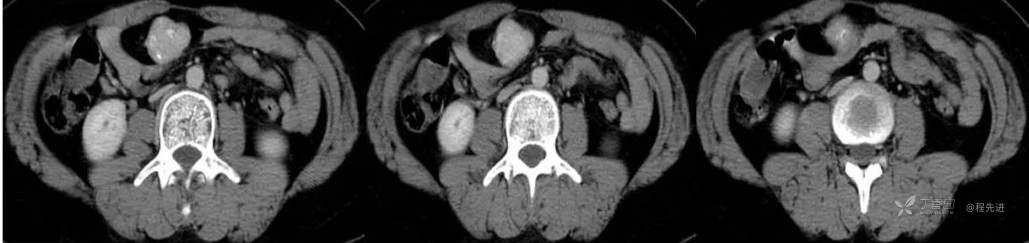

CT

图像依次为平扫(CT值46HU),动脉期(CT值138HU),静脉期(CT值137HU),延时期(CT值96HU)斜矢状位重建